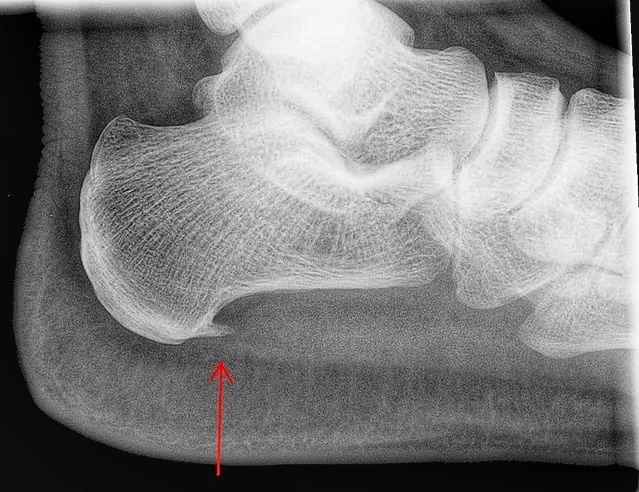

Пяточная шпора, боль при ходьбе

Плантарный фасциит (подошвенный фасциоз) — это заболевание, обусловленное воспалительно-дегенеративными изменениями плантарной (подошвенной) фасции. Подошвенный фасциит является наиболее распространенной причиной боли в пятке, которая особенно сильно ощущается в начале ходьбы (утром при первых шагах). Кроме того, при подошвенном фасциите может болеть свод стопы и лодыжка.

Чаще всего пациентам известно, по названию пяточная шпора.

Хотя, понятия "пяточной шпоры" - не верное. Вырастающая "шпора" - является приспособительным механизмом, реакцией на воспаление подошвенной фасции

При возникновении симптомов описанных выше, следует немедленно обратиться к специалисту. Тот, в свою очередь должен обследовать ногу пациента и обязательно провести исследование рентгеном, только тогда доктор сможет точно определить тяжесть заболевания и назначить эффективный метод лечения.